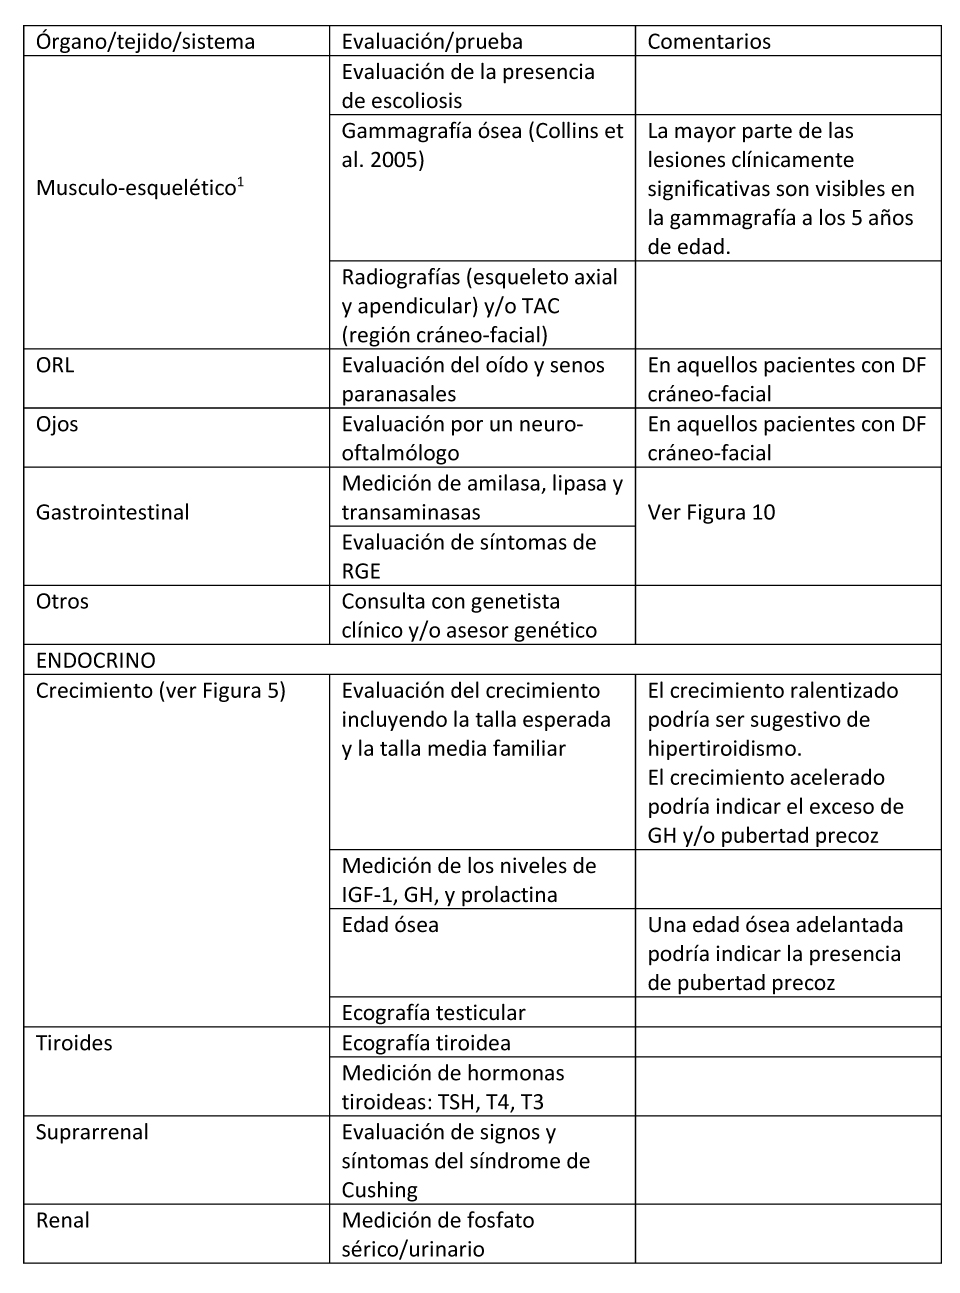

Tabla 2. Evaluaciones recomendadas tras el diagnóstico inicial en individuos con Displasia Fibrosa/Síndrome de McCune-Albright

(1) Ver Figura 3 en la que se exponen los estudios recomendados para evaluar el esqueleto tras el diagnóstico. ORL: sistema otorrinolaringológico; RGE: reflujo gastro-esofágico.